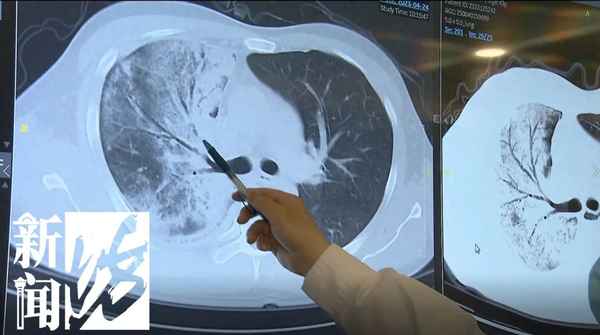

右肺因感染

几乎丧失肺功能

据了解,

吴先生入住中山医院时,

他的一肺因感染

已经几乎没有肺功能了。

医生:右上肺、右下肺都是实变,实变意味着肺泡被炎症的渗出液充填,右肺没有呼吸功能,就是没有通气和换气的功能,也就是说这个病人会引发呼吸衰竭。